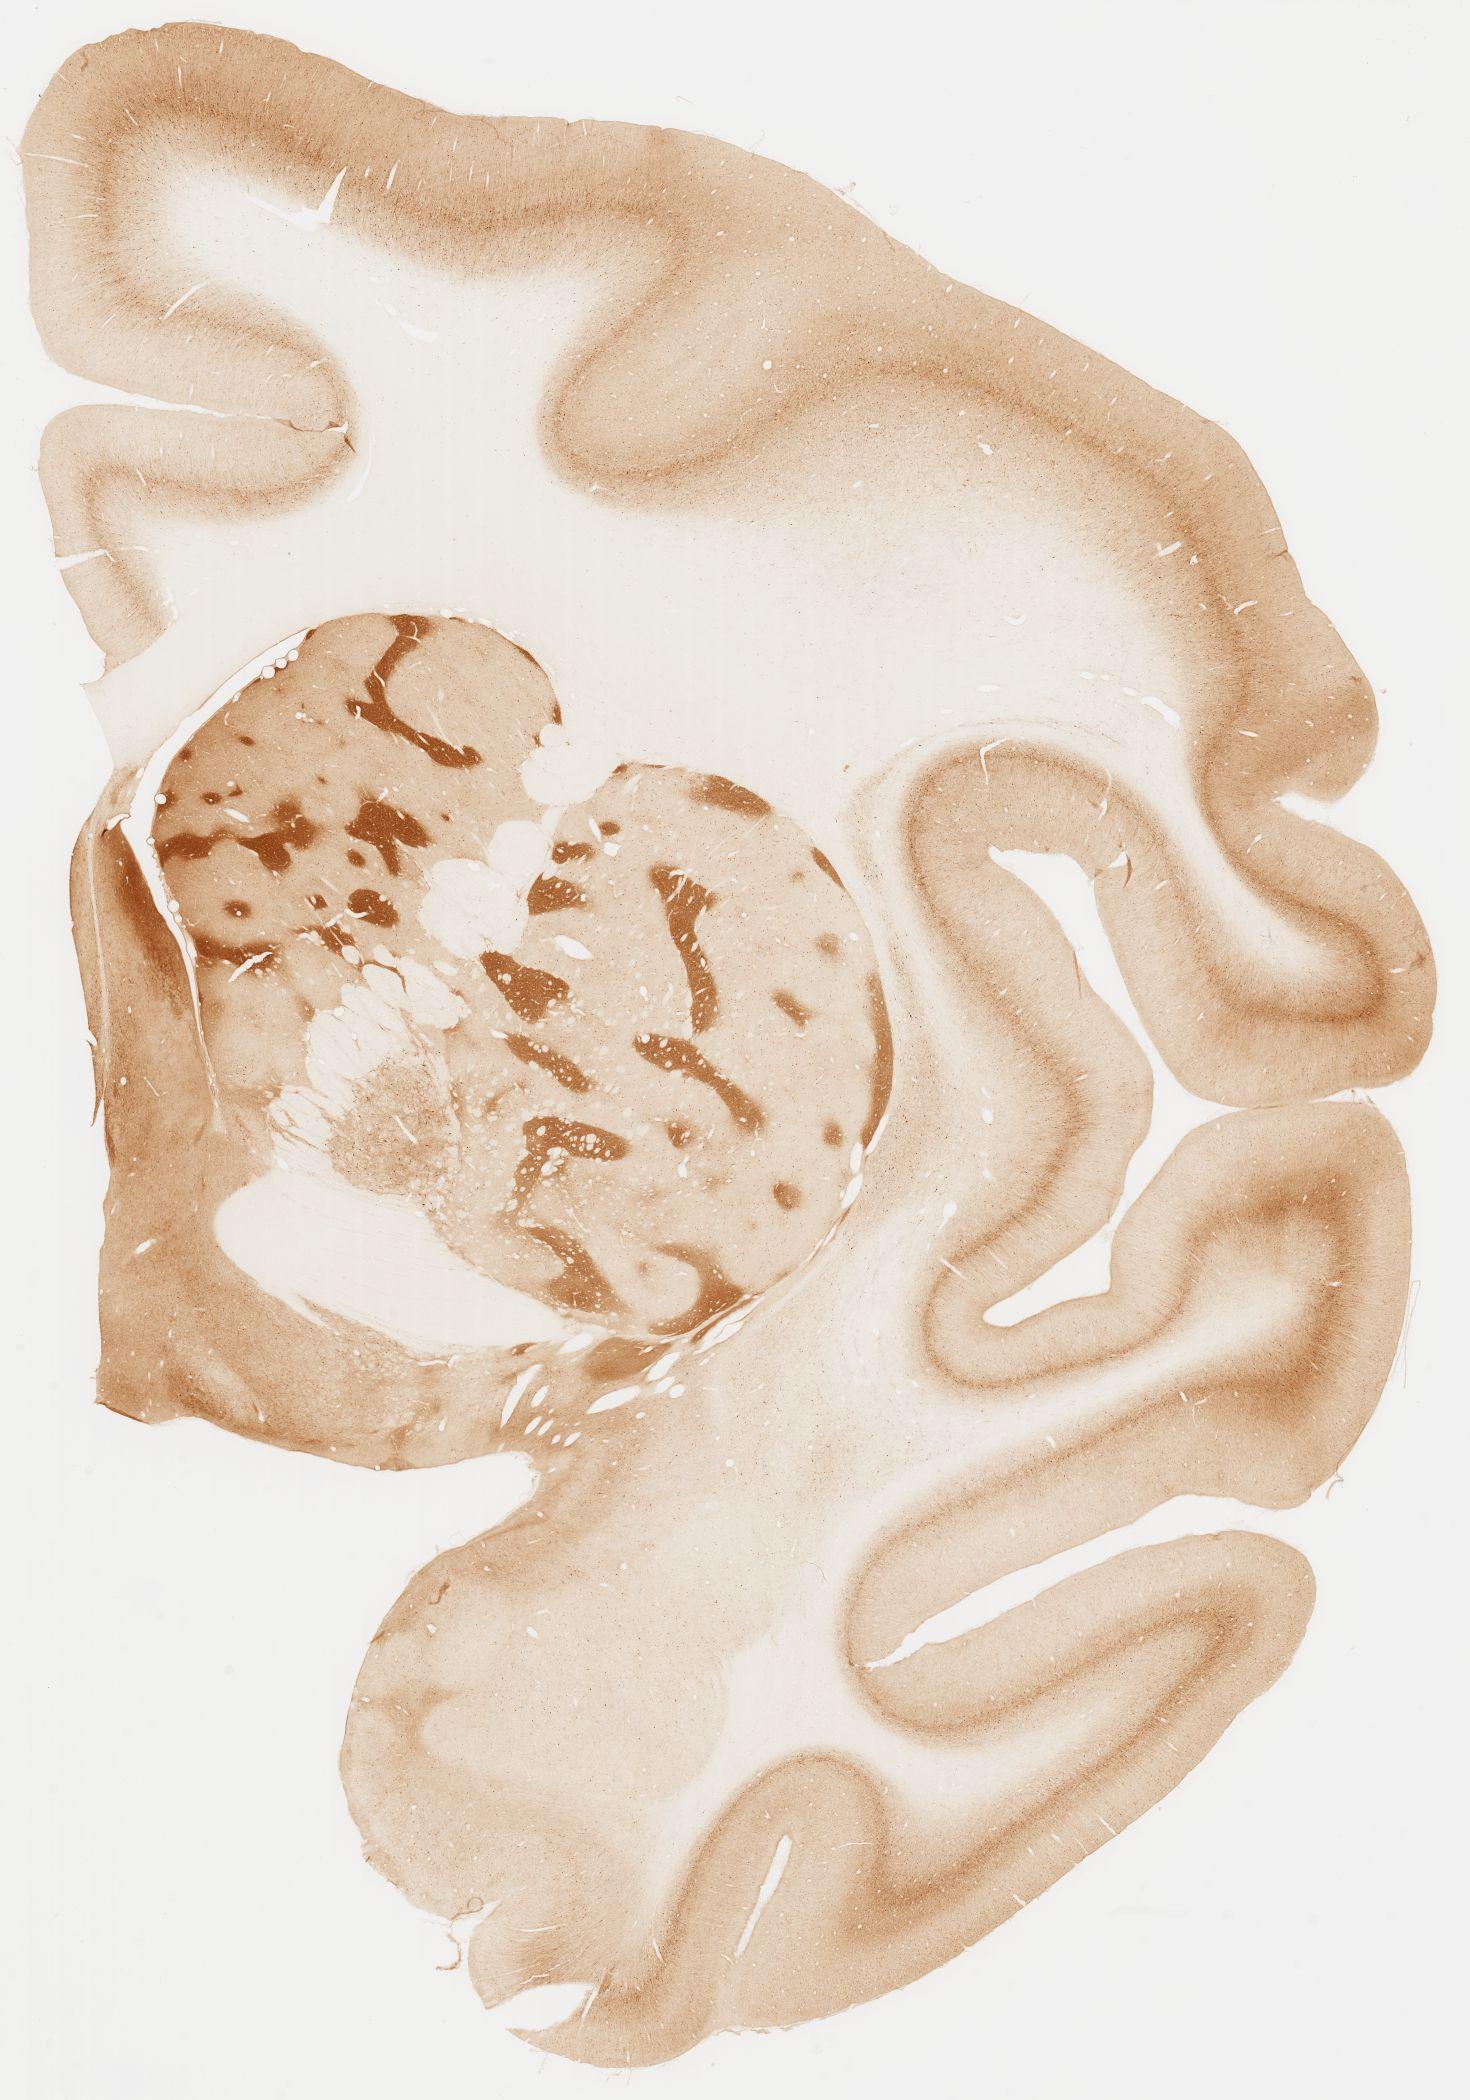

Datasets -> Macaca Fascicularis -> KChIP1, (Potassium Voltage-Gated Channel-Interacting Protein 1), coronal, immuno, Whole-Brain, adult

[ Metadata ]   ·   Source: Edward G. Jones

Displaying Sections 41 thru 80 of 92 Sections for this Dataset